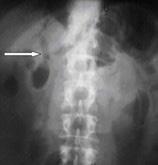

El examen radiológico más importante en la perforación de víscera hueca es la radiografía de abdomen simple en bipedestación teniendo como hallazgo neumoperitoneo, signo de las alas de gaviota si es bilateral, o signo de Popper si es unilateral.

Figura 69. Lavado peritoneal diagnóstico LPD ECO - FAST TAC Tabla 4 . Diferencias entre los procedimientos diagnósticos en trauma abdomina Figura 70. Neumoperitoneo. Elevación de ambos hemidiafragmas